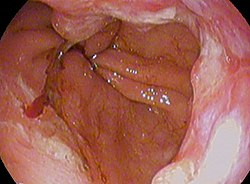

110I61 | 食道癌 国試 | M3E Medical

110I61 | 食道癌 国試 | M3E Medical

110I61 | 食道癌 国試 | M3E Medical,

110I61 | 食道癌 国試 | M3E Medical, 食道外科 | 国立がん研究センター 中央病院,

食道外科 | 国立がん研究センター 中央病院, 食道癌を再発させない戦略に大きな進歩:日経メディカル,

食道癌を再発させない戦略に大きな進歩:日経メディカル, 食道癌 - Wikipedia,